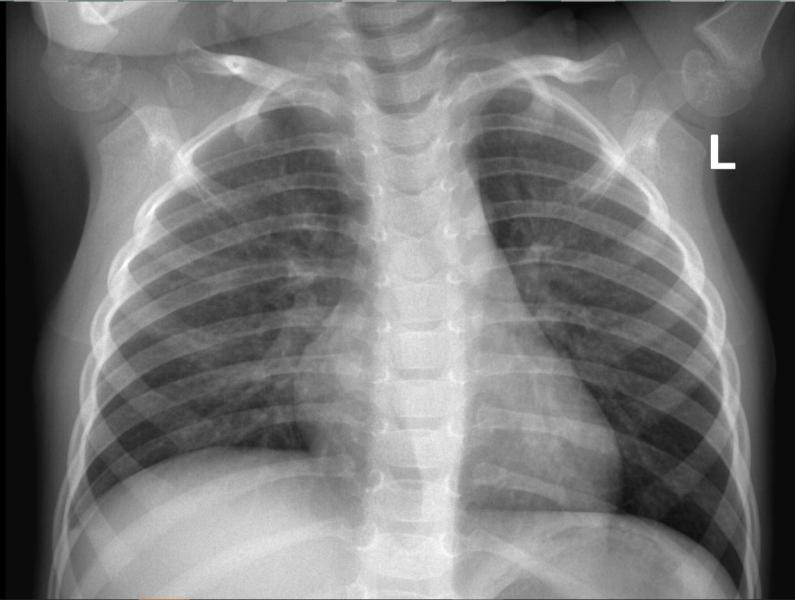

Рентгенологи, нужна помощь! Что видите на снимке? Описание, подозрения и ваши заключения.

post image 2

Есть тут специалисты - рентгенологи?⁉️ Кто видит что?!